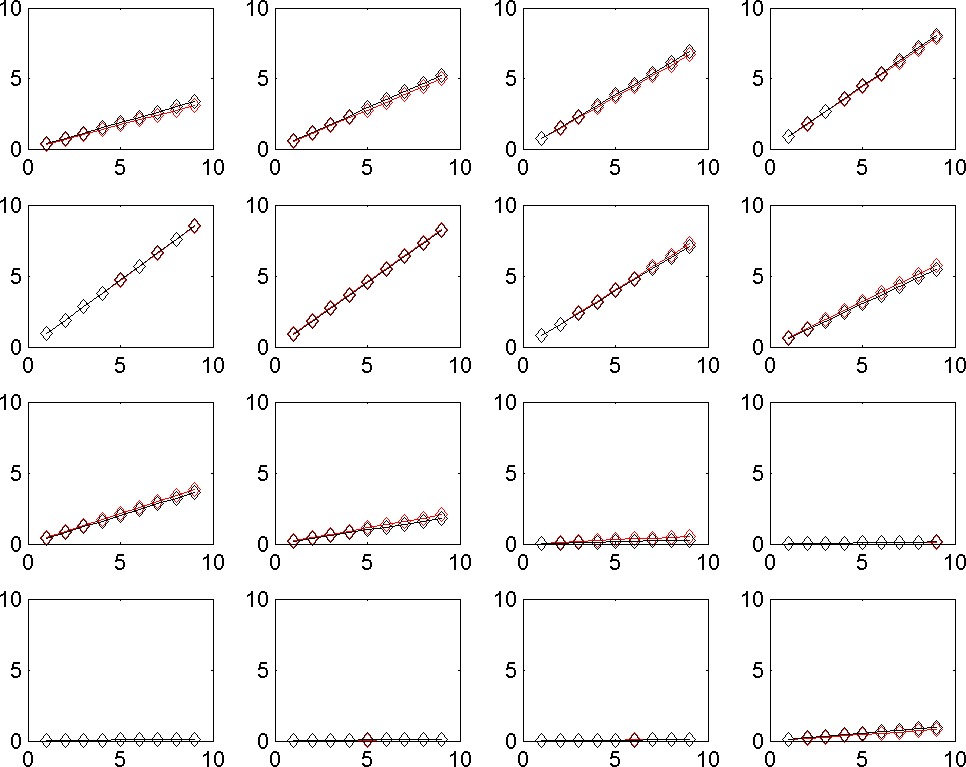

Fig. 4 represent the results of the proposed method for both horizontal, vertical and absolute displacement. To better be able to compare the results, the ring is divided into 16 sub-regions and the results of ANSYS and MATLAB implementations are compared. Fig. 5 shows the average displacement in each region for 10 iterations of pressure increment for both ANSYS and proposed method. Based on the provided results, it can be seen that the proposed model is consistent with the results of ANSYS, even in regions with low mobility (regions 11, 12, 13 and 14).